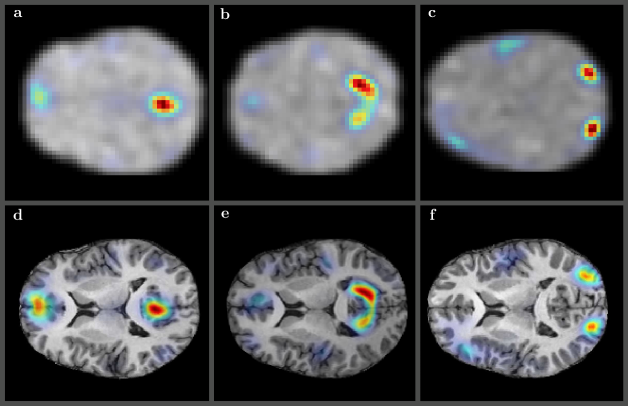

Refer to caption

Fig 7: Several randomly selected resting state modes obtained using low resolution (64x64x30) rs-FMRI volume registered to T1 high resolution (290x262x262) anatomical volume – default mode (a) and (d), visual lateral (b) and (e), and visual occipital (c) and (e) – for some of the subjects from Figure 2. The upper panels (a, b, and c) show the original low resolution rs-FMRI modes. The symplectomorphic maps in lower panels (d, e, and f) show accurate localizations of functional modes in the appropriate regions of HRA volumes.

Figure 7 shows comparison of original and registered images for several of the resting state functional modes obtained using our entropy field decomposition (EFD) technique [79, 80]. The default mode (a) and (d), the visual lateral (b) and (e), and the visual occipital (c) and (f) modes are shown for some of the subjects from Figure 2. The symplectomorphically mapped images overlayed over correspondent HRA slices (d, e, and f) show very accurate localization of functional modes in the appropriate regions of HRA volumes.